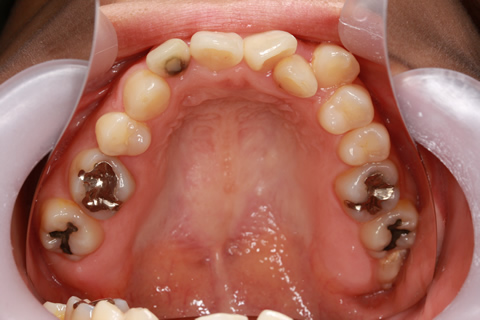

受け口(反対咬合)の症状

下あごが上あごより突出しているか、上あごが下あごより後退している状態で、咬み合わせが逆になっているので反対咬合ともいいます。お子様の場合、受け口(反対咬合)を放置していると、成長期において下あごが過大に成長し悪化しますので、出来る限り早い時期に治療することをおすすめします。受け口(反対咬合)は見た目の問題だけでなく顎の動きを制限し、将来的に顎の痛み(顎関節症)を引き起こす場合があります。また、お子様の場合は、正常な上顎の成長を阻害する可能性があります。

受け口(反対咬合)の症例